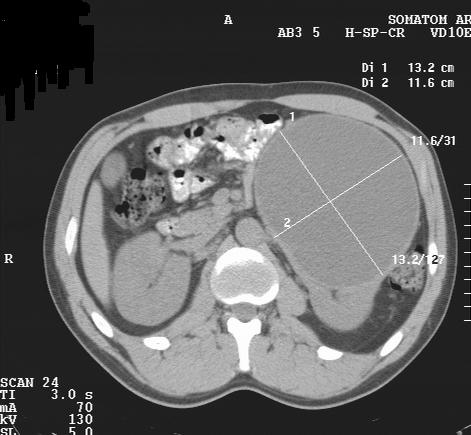

Вложения

2.JPG

3.JPG

4.JPG

КТ сделали без контрастирования, смысл такого КТ??? Диагностической ценности-ноль.

Dr.Mario писал(а):КТ сделали без контрастирования, смысл такого КТ??? Диагностической ценности-ноль.

Ценность бывает не только диагностическая